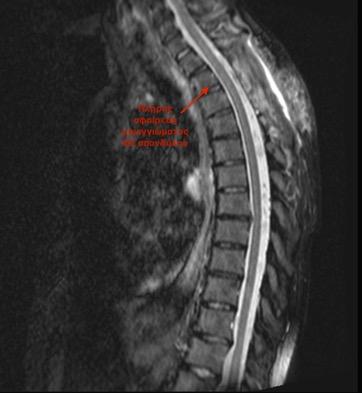

τους έξι μήνες. Το επενδύμωμα της σπονδυλικής

στήλης διακρίνεται σε εξωμυελικό (οσφυϊκής μοίρας) και σε ενδομυ-

ελικό (αυχενικής μοίρας). Το επεν-

δύμωμα της οσφυϊκής μοίρας είναι το συχνότερο και συναντάται στο επίπεδο του Ο1-Ο2 σπονδύλου και